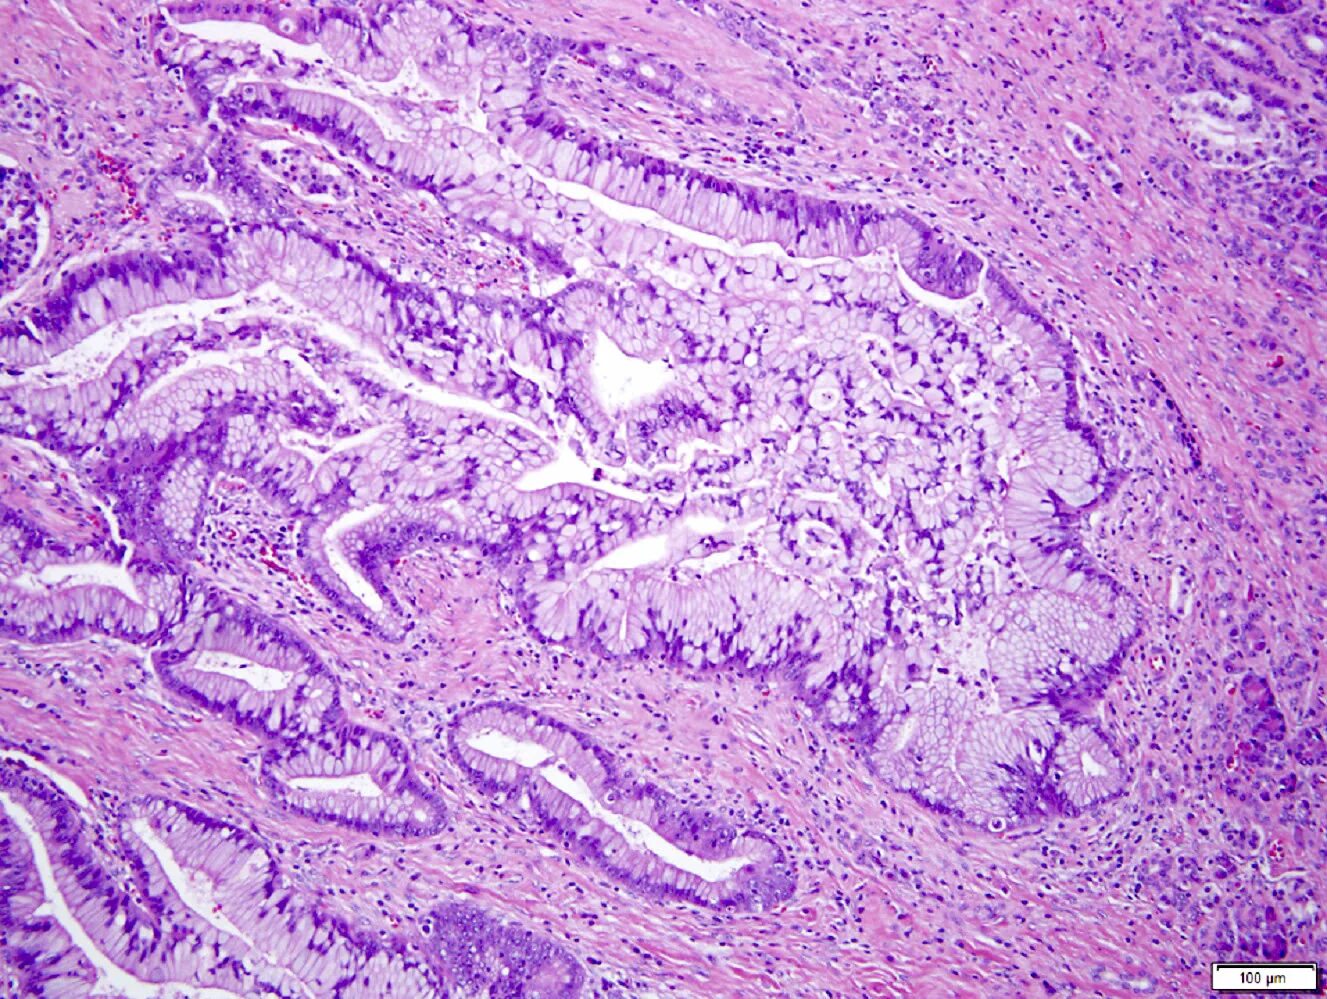

Гистологические варианты